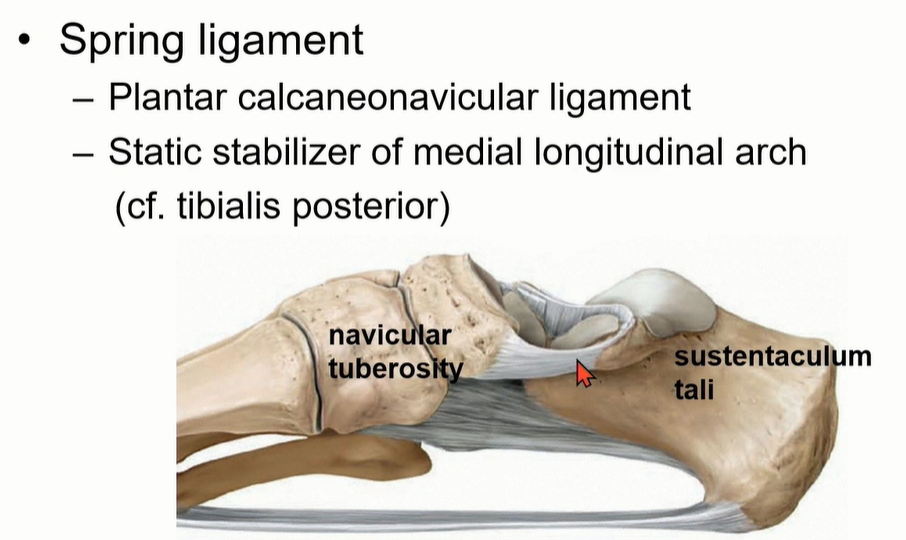

스프링 ligament는 plantar calcaneonavicular ligament라고 부르고, navicular tuberosity와 sustentaculum tali를 이어주는 인대이다. Medial longitudinal arch의 static stabilizer 중에 하나임. (다른 하나는 TP tendon )

-> Flat foot의 경우에는 2개의 static stabilizer 평가가 중요하다.

Spring ligament는 1-3으로 구성되어 있다. complex임.